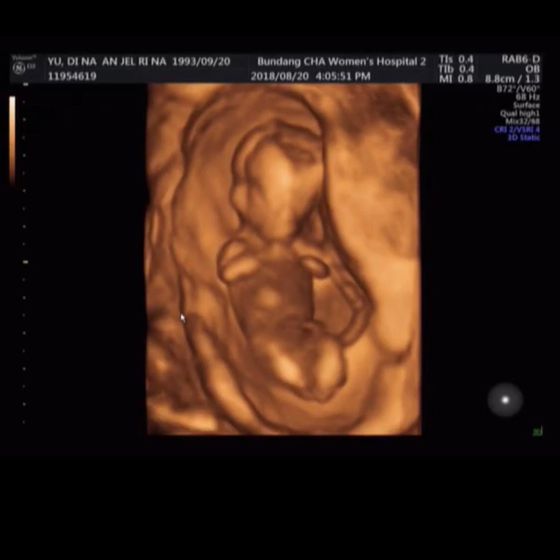

Первый скрининг! У нас все отлично! Я так рада, просто нет слов ❤️ Так переживала, дурные мысли в голову лезли пока не увидела моего малыша ❤️ как он шевелится внутри меня ❤️ не забываемо ? Мы с мужем заплакали от счастья! Желаю всем слышать только хорошие новости от наших врачей ?